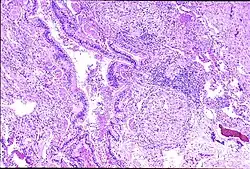

![]() | |

| Peribronchal non-necrotizing granuloma from berylliosis | |

Granuloma formation is seen in other diseases such as tuberculosis and sarcoidosis. Sarcoidosis, like berylliosis, also produces granulomas without a necrotic core, and so distinction between the two processes can be difficult.